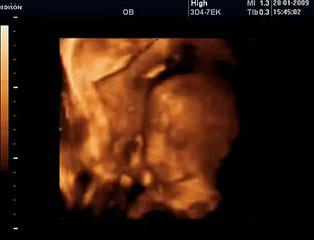

BCF Ultrason Görüntüsü - Hasvet Medikal